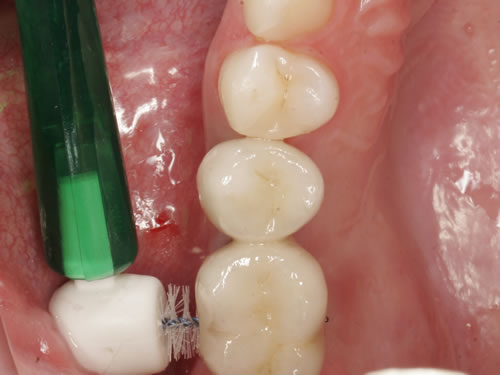

9 Implantatpflege

Es wurde schon darauf hingewiesen, dass für den Langzeiterfolg die Mundhygiene einen wesentlichen Beitrag leisten muss. Mindestens zweimal täglich sollten die Zähne und besonders die künstlichen Pfeiler gründlich gereinigt werden. Dabei ist der Bereich wichtig, in dem das Implantat durch die Schleimhaut tritt. Geringste Ablagerungen von Belägen (Plaque) oder Zahnstein (Abb. 9.1, 9.2) können bereits Entzündungen zur Folge haben und das Implantat gefährden. Jede Entzündung hat eine Taschenbildung der Schleimhaut zur Folge. Damit wird der dichte Abschluss um die Pfeiler aufgelöst. Bakterien und Speisereste können aus der Mundhöhle in die Tiefe gelangen und eine ernste Knochenentzündung hervorrufen. Dies führt zu einem Knochenabbau und schließlich zum Verlust der Implantate.

Für die intensive Pflege stehen verschiedene Hilfsmittel zur Verfügung (Abb. 9.3 bis 9.6).

Zunächst werden Zähne und Implantate mit einer Zahnbürste und Zahnpasta von außen und innen gereinigt (Abb. 9.5). Auch der Einsatz elektrischer Zahnbürsten kann hier sinnvoll sein.

Zusätzlich müssen aber die Pfeiler zwischen den Zahnkronen oder den Stegelementen gesäubert werden. Dazu sind kleine Bürstchen geeignet, die von außen und innen zwischen den Zähnen und Implantaten hindurchgeführt werden (Abb. 9.6 bis 9.9).

Diese Bürsten werden als Zahnzwischenraumbürsten oder Interdentalbürsten bezeichnet; sie sind Einmalartikel oder mit austauschbaren Ansätzen erhältlich. Sie können natürlich nur dann eingesetzt werden, wenn die Kronen und Brücken so gearbeitet wurden, dass ein genügend großer Zwischenraum vorhanden ist.